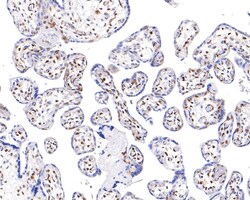

Invitrogen™ Phospho-ATF2 (Thr71) Recombinant Rabbit Monoclonal Antibody (SC05-90)

The transcription factor ATF-2 (also called CRE-BP1) binds to both AP-1 and CRE DNA response elements and is a member of the ATF/CREB family of leucine zipper proteins. ATF-2 interacts with a variety of viral oncoproteins and cellular tumor suppressors and is a target of the SAPK/JNK and p38 MAP kinase signaling pathways. Various forms of cellular stress, including genotoxic agents, inflammatory cytokines and UV irradiation, stimulate the transcriptional activity of ATF-2. Cellular stress activates ATF-2 by phosphorylation of Thr69 and Thr71. Both SAPK and p38 MAPK have been shown to phosphorylate ATF-2 at these sites in vitro and in cells transfected with ATF-2.

| Immunohistochemistry (Paraffin), Western Blot, Immunocytochemistry | |